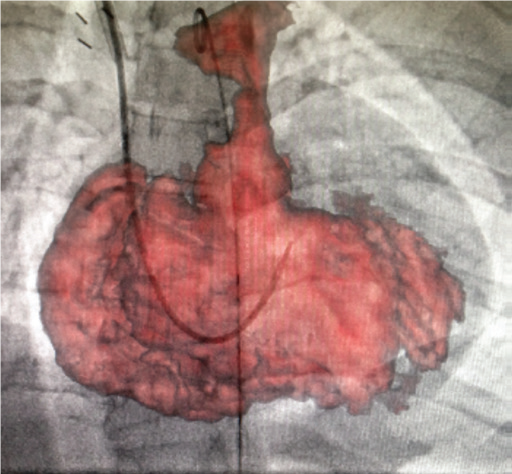

Встановлення стенту

Встановлення клапану Melody®

Контрольна ангіографія

Завдяки маркерам співставляють МРТ об’єм зі скопічним зображенням.

Для точного співставлення використовують рентген зображення в прямій та боковій проекціях.

3D анатомія використовується як дорожня карта (так зв. Roadmap)

Накладений 3D об‘єм полегшує маніпуляцію катетером через складну анатомію пацієнта, допомогає точно розташувати стент і клапан легеневої артерії.